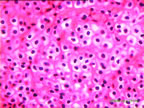

Bağ dokusu, organizmadaki çeşitli doku veya organları birbirine bağlayan dokudur. Bu doku, yumuşak organları korur ve onlara desteklik sağlar. Bağ dokusu vücudun savunmasında da görev alır.Bu doku, bağ dokusu hücreleri, hücreler arası maddeler ve liflerden oluşmuştur.

Örnek: Görevi dokuların beslenmelerini, korunmalarını, dokular arası alanların dolmasını ,yağın depolanmasını,kan hücrelerinin üretimini ,enfeksiyona karşı korunmayı sağlar.